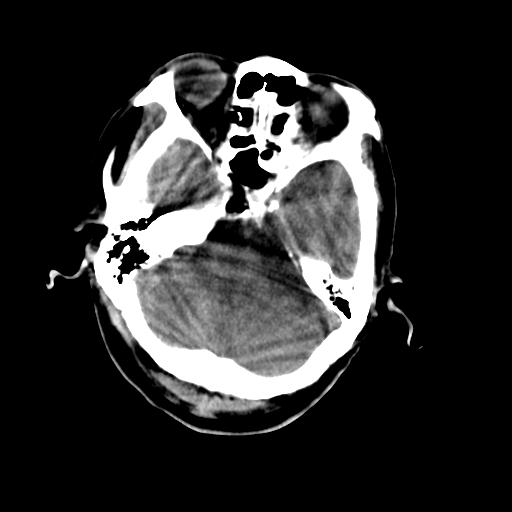

男,78岁。自诉两周前因右侧肢体障碍行ct检查,诊断为脑梗塞(患者ct片已丢失)治疗好转后出院。现因意不清12小时,又行ct检查。

结合病史考虑中性脑出血并脑疝形成,血肿破入下腔及脑室.

结合病史考虑左侧额颞顶叶出血性脑梗塞。